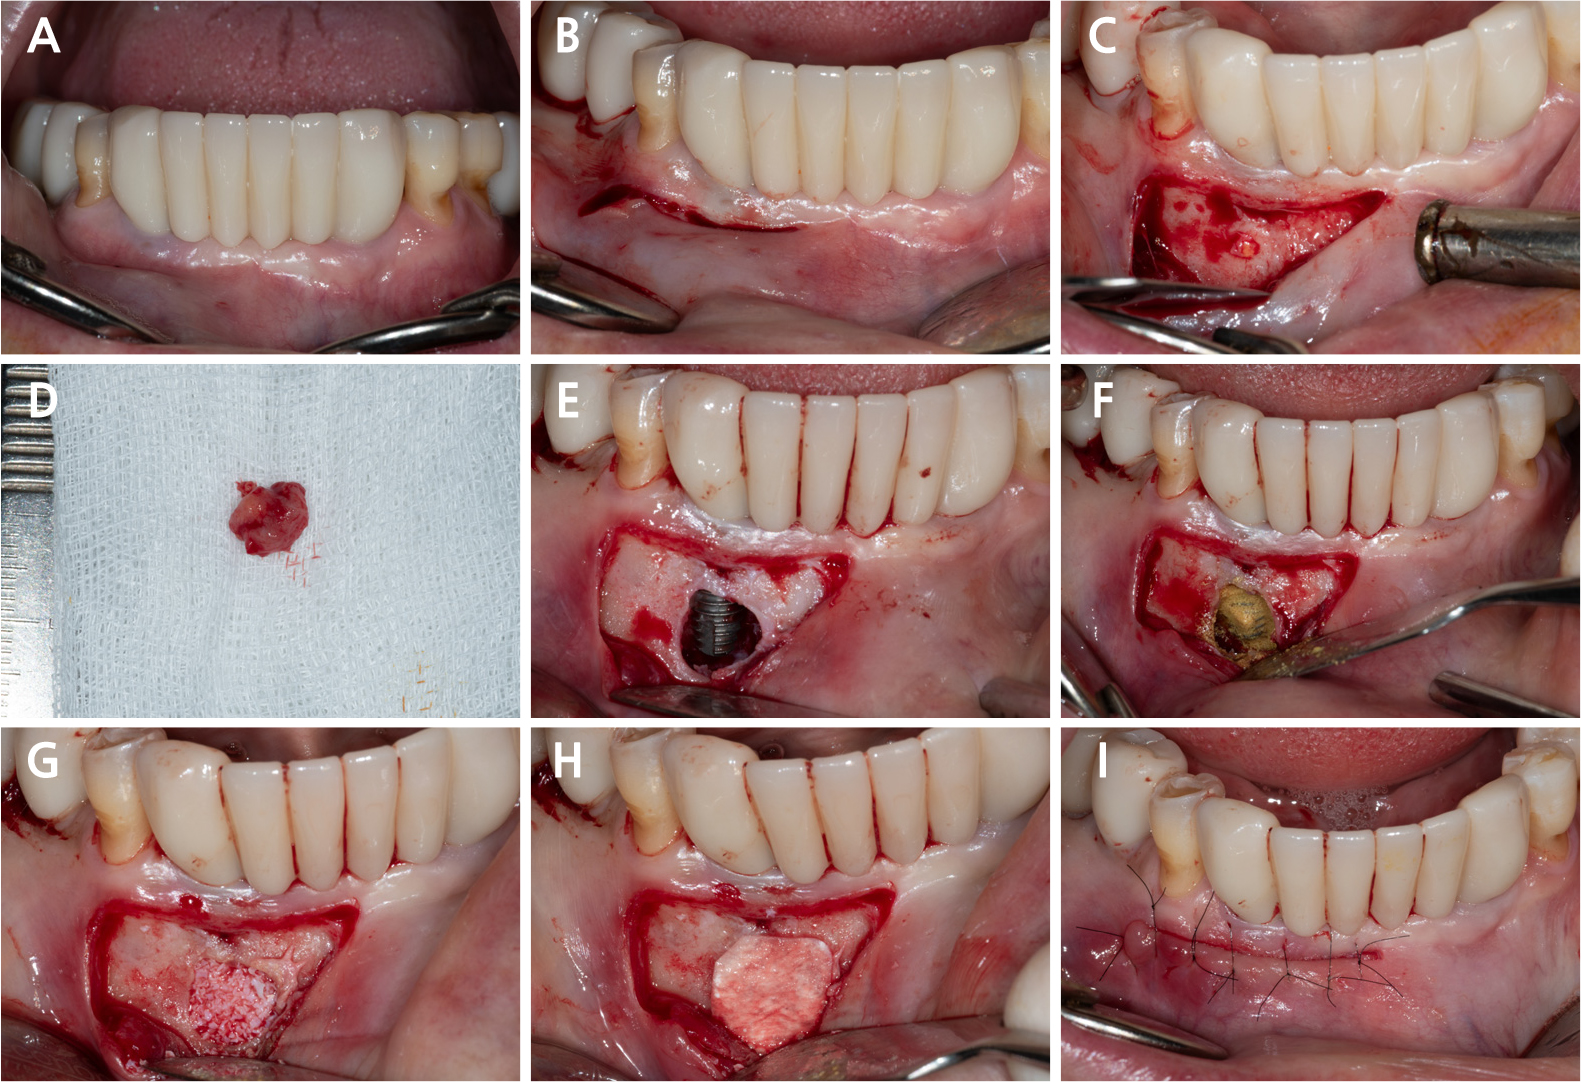

- Reconstructive Approach for Treatment of Retrograde Peri-implantitis in Mandibular Canine Region: A Case Report

- Dae-Young Kang

- Retrograde peri-implantitis (RPI) is a localized inflammatory lesion around the apex of a dental implant, typically occurring shortly after implant placement or …

- Retrograde peri-implantitis (RPI) is a localized inflammatory lesion around the apex of a dental implant, typically occurring shortly after implant placement or prosthetic loading. This report describes the clinical management of RPI in a 62-year-old female patient who presented with tenderness and a sinus tract in the mandibular canine region. Radiographic examination confirmed a periapical radiolucency around implant #43, with intact crestal bone. A reconstructive approach was employed through a buccal window following flap elevation. Granulation tissue was removed, and implant surface decontamination was performed using a titanium brush and adjunctive tetracycline hydrochloride scrubbing. The defect was grafted with deproteinized porcine bone mineral and covered with a collagen membrane. Healing progressed favorably, with symptom resolution and radiographic bone fill observed at the 1.5-year follow-up. This case demonstrated that, when appropriate defect morphology and surgical access are present, RPI can be effectively treated using a reconstructive approach. Preoperative cone-beam computed tomography is essential to assess accessibility, and regular periapical monitoring is advised for patients with prior endodontic pathology to enable early diagnosis and intervention. - COLLAPSE